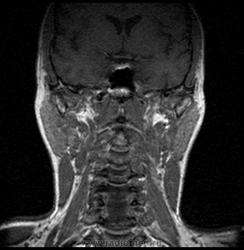

06.06.2011 МРТ - головы и шеи.

Пацентка 36 лет, с жалобами на припухлось в околоушной области справа.

В глубокой доле  правой околоушной железы  на фоне неизмененной паренхимы зона  гетерогенного по Т2, гипоинтенсивного по Т1  с единичными гиперинтенсивными включениями.При контрастировании- накопление контраста диффузное неоднородное и по периферии.Рискну предположить злокачественное образование ( аденокарцинома) с низкой степенью злокачественности( есть капсула, экспансивный рост).Сильно не расстреливайте.

Проблема в том, что перед челюстно-лицевым хирургом стоит распространенность любого объемного процесса, в данном случае все упирается в возмможную травму лицевого нерва и конечно же с дальнейшим его парезом, а ведь женщина  еще молодая. Образование имеет тонкостенную оболочку, по структуре неоднородно, с наличием кальцината, при этом МР-сигнал от окружающих анатомических структур(как костных так и мышечных) не изменен, т.е. об инфильтративном росте речи не идет, в какой то степени доброкачественное. В конкретном случае лицевой нерв с ретромандибулярной веной просто несколько оттеснен.

По гистологии аденома околоушной слюнной железы, но после удаления пока сохраняется парез лицевой мускулатуры, возможно временный.